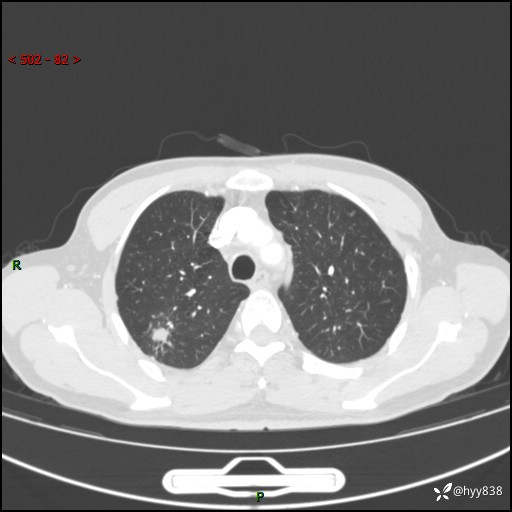

69岁/男,发现肺部病变6天。该有的征象都有,肉芽肿 VS 肿瘤,一念之间---(有结果)

主诉:发现肺部病变6天。

现病史:患者6天前于我院泌尿外科住院,住院期间行胸部CT检查,提示“肺部病变”,患者无畏寒、发热、盗汗、咳嗽、咳痰、咯血、胸痛、呼吸困难,无反酸、腹痛、腹泻、头痛、头晕等不适。未予特殊处理,现为进一步诊治,门诊以“肺肿物”收入我科。 患者本次起病以来,精神食欲尚可,大小便正常,体力及体重无明显变化。

胸部CT平扫+增强